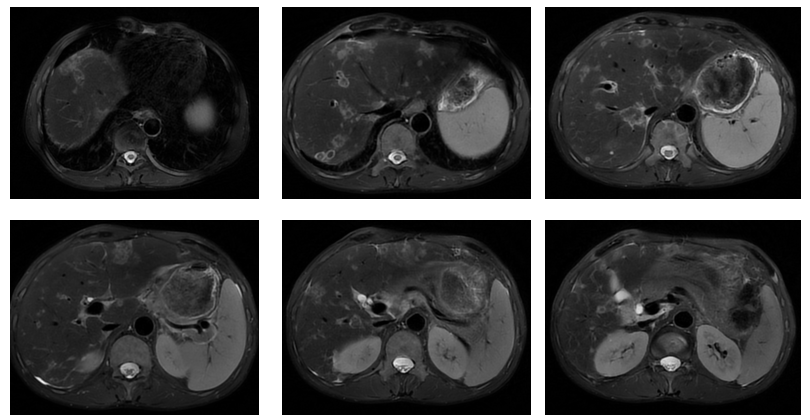

维迪西妥单抗联合方案治疗2周期后复查,肿瘤标志物:CEA 65ng/ml,CA199>1000ng/ml,CA724 26ng/ml;影像学提示肝脏病灶较前明显缩小(图2),疗效评价为部分缓解(PR)。

维迪西妥单抗联合方案治疗4周期后复查,肝脏病灶进一步缩小,疗效评估为持续PR。肿瘤标志物水平进一步大幅下降:CEA 8ng/ml,CA19-9 214ng/ml,CA72-4 6ng/ml。